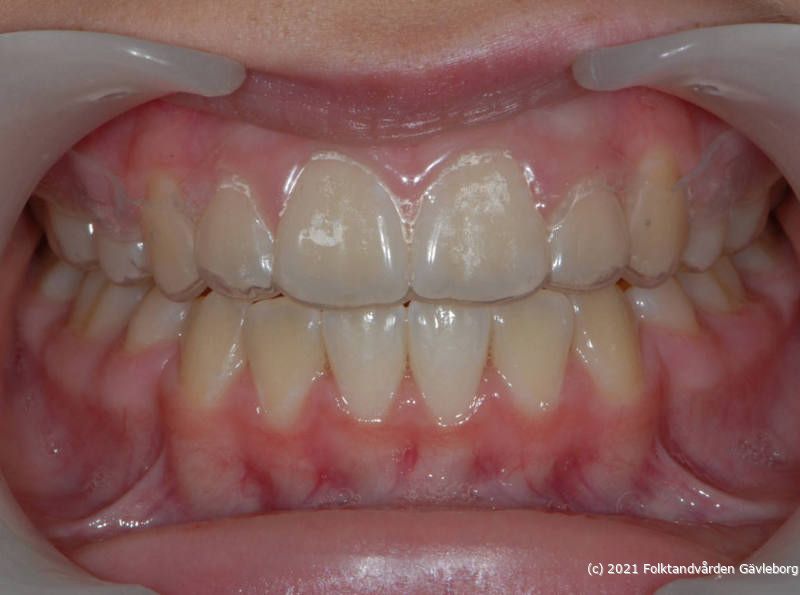

På ortodontiklinikerna diagnostiserar och behandlar vi bettfel på både barn och vuxna. Alla våra patienter kommer på remiss till oss. Vi behandlar bettfelen med fastsittande och avtagbar apparatur. Hos oss behandlas också de patienter som har avvikelser i käk- och ansiktsskelettet och som kräver tandreglering inför rekonstruktiv kirurgi. Vi har ett nära samarbete med allmäntandvård, privattandvård och övrig specialisttandvård i länet samt ett gott samarbete med Akademiska Sjukhuset i Uppsala när det gäller barn med olika syndrom och läpp-käk-gomdefekter. Våra specialistkliniker finns i Gävle och Hudiksvall.

Här nedan hittar du några exempel på vanligt förkommande behandlingar. Hittar du inget som passar det du vill visa, gå in på menyn ovan genom att föra musen över "Information". Navigera sedan till respektive apparatur. Klickar du på rubriken "Visa alla bilder" får du upp samtliga apparaturer som finns här.